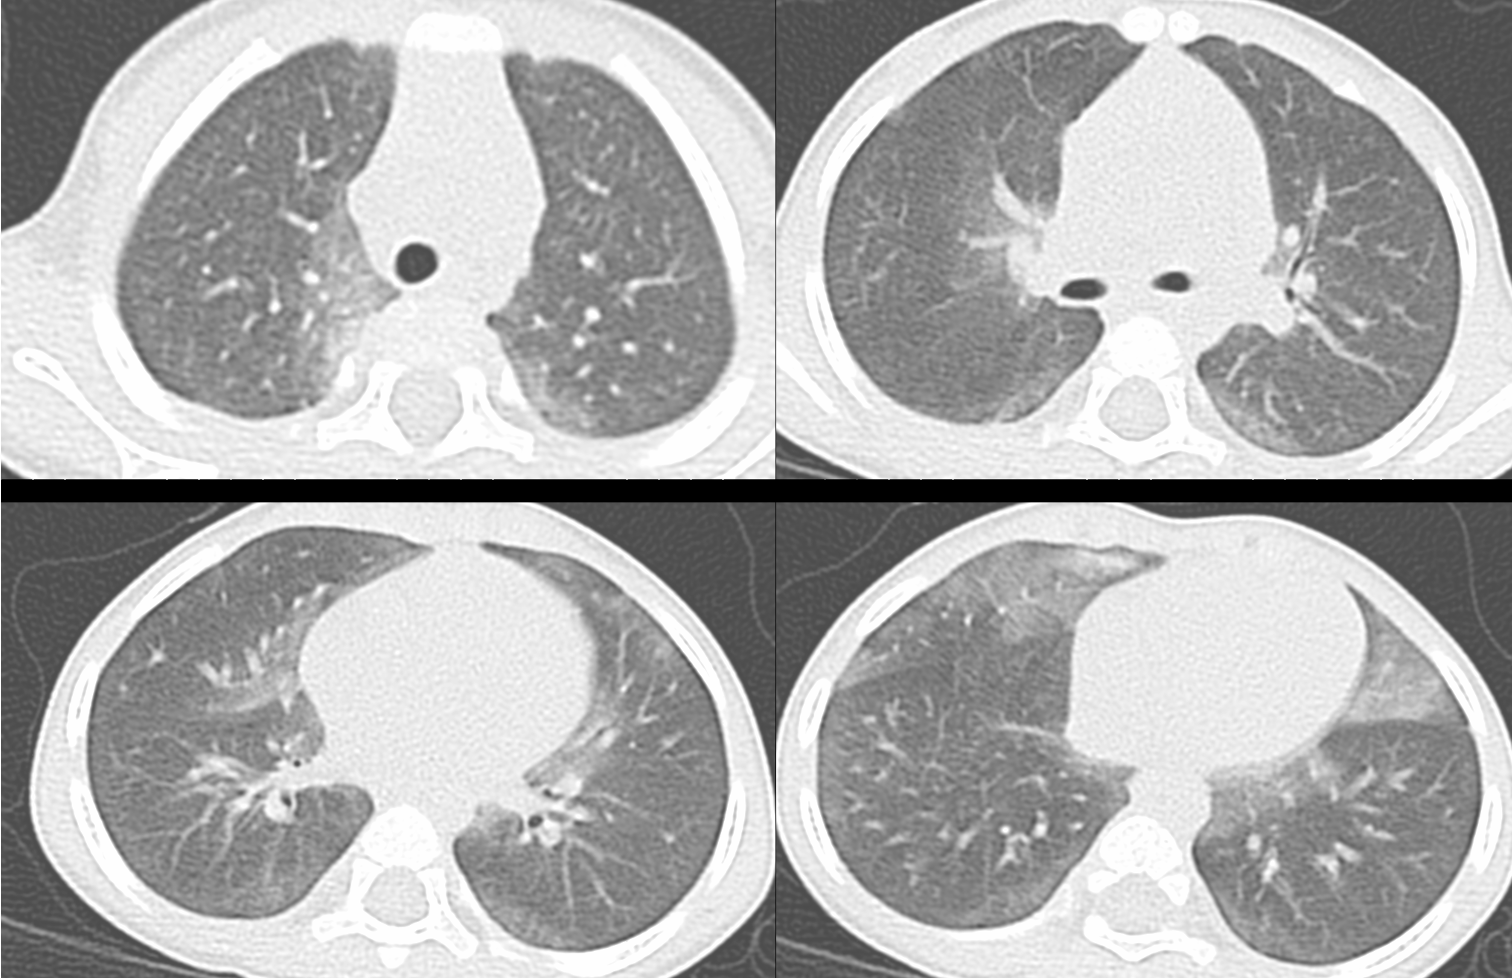

Case 106: A Specific Pattern of Ground Glass in an Infant

Most infants with chILD present with ground glass, which in most instances is non-specific, except in this one condition.

A 6 mths old came with dyspnea

- Neuroendocrine cell hyperplasia of infancy (NEHI)

- Pulmonary interstitial glycogenesis (PIG)

- Surfactant dysfunction

- Hypersensitivity pneumonitis

The video below discusses the CT findings, the differentials, two other cases, the final diagnosis and how to approach such patients.